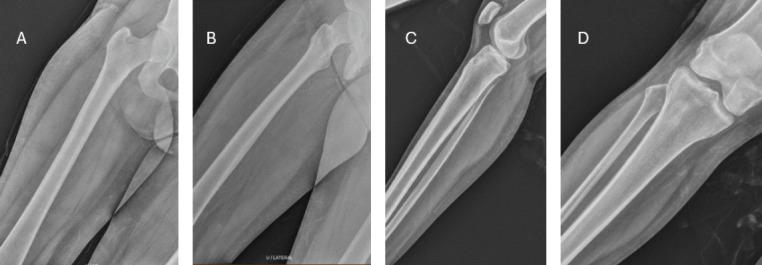

A 24-year-old otherwise healthy female patient presented with acute-onset pain of right mid shaft of femur and proximal tibia. She had a normal radiograph with raised inflammatory parameters. She had a hypointense lesion in the T1-weighted imaging, features suggestive of osteomyelitis. A second lesion hyperintense lesion on T2-weighted magnetic resonance imaging (MRI) was seen in the proximal tibia with a fracture line in the anteromedial cortex of proximal tibia of the right leg, possibly osteomyelitis. The patient was taken up for open biopsy, sampling for culture and debridement. The culture grew Salmonella spp. The patient was treated with 6 weeks on intravenous ertapenem and 2 weeks of oral cotrimoxazole. She was completely symptom free by 6 weeks and repeat MRI at 6 months showed healed status of the index site.